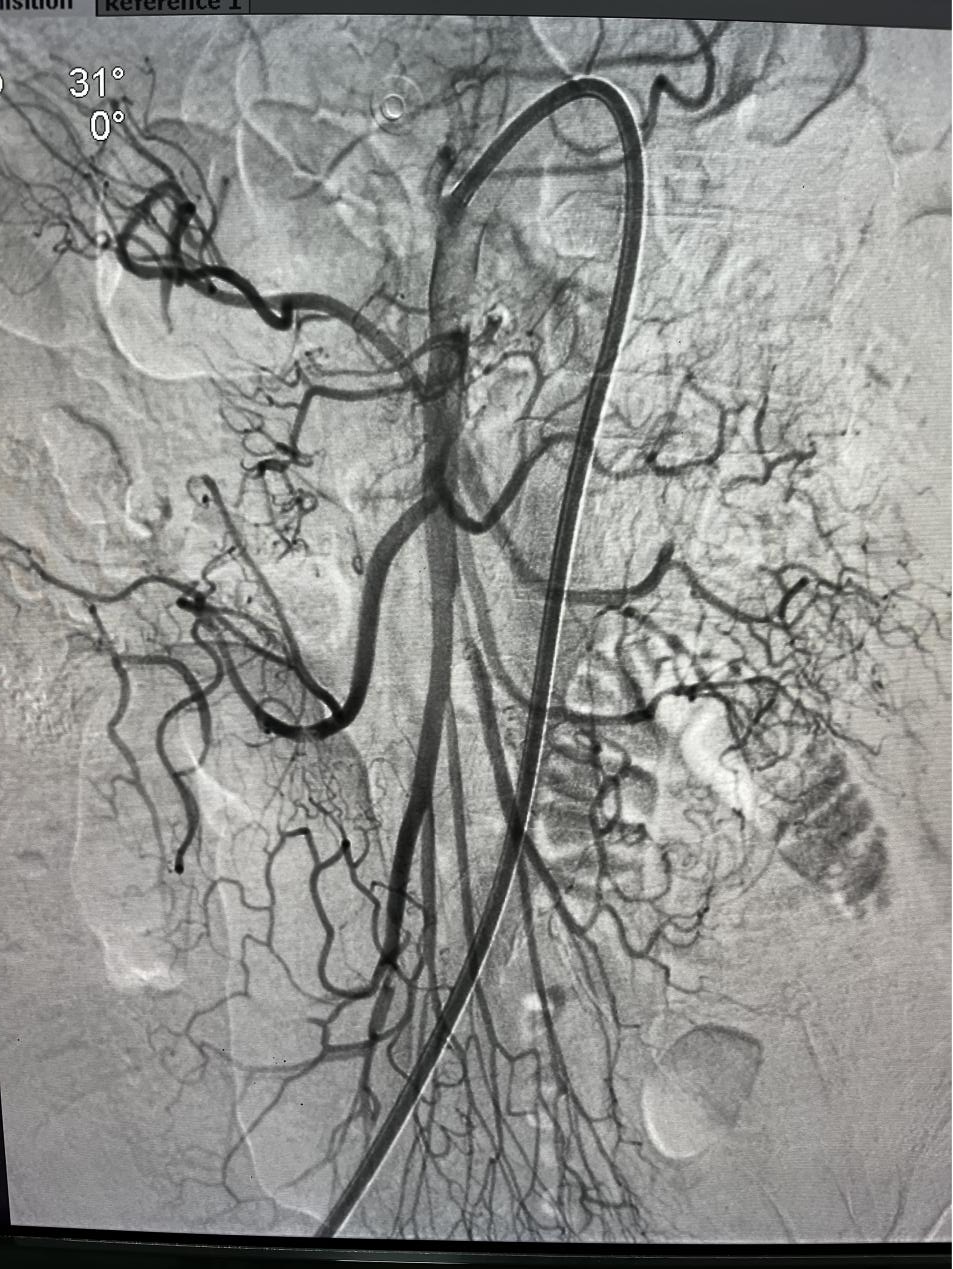

一切准备妥当,医护人员以最快的速度将她送入导管室,车星从腹股沟穿刺,造影提示肠系膜上动脉主干明显血流中断,赶紧取栓。

注:肠系膜上动脉血流立马恢复,各分支动脉也有了血流

血栓被取出后,效果立竿见影,肠系膜上动脉血流立马恢复,各分支动脉也有了血流,手术成功,老人的腹痛即刻得到缓解。